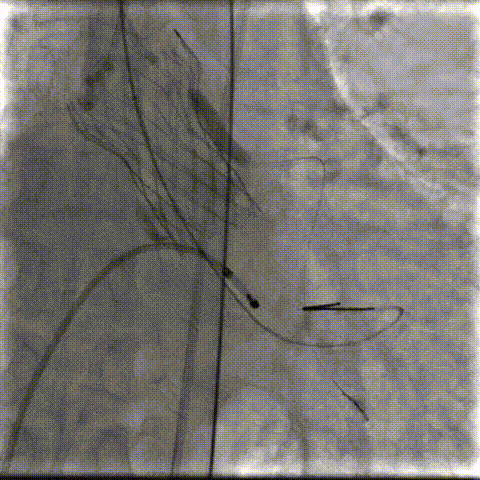

术中影像:

双侧侧髂血管造影血管纤细

LCA保护下18mm球囊预扩,扩张充分,瓣叶向LCA开口偏移;输送器过弓顺利。

瓣环下精准定位稳定释放,瓣膜工作位造影考虑瓣叶推挤LCA阻挡临界状态,释放“烟囱支架”。

瓣膜稳定脱钩,20mm球囊后扩,“烟囱支架”Kissing,后扩后支架形态改善。

左髂动脉“翻山“,造影+覆膜支架预备伴随保护下顺利退鞘,造影观察无血管损伤,手术顺利结束。